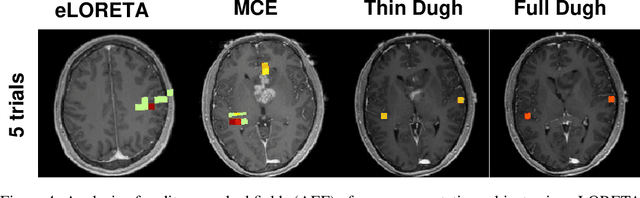

Abstract:Several problems in neuroimaging and beyond require inference on the parameters of multi-task sparse hierarchical regression models. Examples include M/EEG inverse problems, neural encoding models for task-based fMRI analyses, and climate science. In these domains, both the model parameters to be inferred and the measurement noise may exhibit a complex spatio-temporal structure. Existing work either neglects the temporal structure or leads to computationally demanding inference schemes. Overcoming these limitations, we devise a novel flexible hierarchical Bayesian framework within which the spatio-temporal dynamics of model parameters and noise are modeled to have Kronecker product covariance structure. Inference in our framework is based on majorization-minimization optimization and has guaranteed convergence properties. Our highly efficient algorithms exploit the intrinsic Riemannian geometry of temporal autocovariance matrices. For stationary dynamics described by Toeplitz matrices, the theory of circulant embeddings is employed. We prove convex bounding properties and derive update rules of the resulting algorithms. On both synthetic and real neural data from M/EEG, we demonstrate that our methods lead to improved performance.